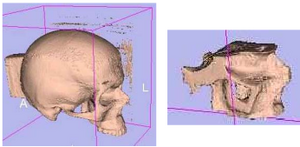

Publication: J Craniomaxillofac Surg. 2016 Feb;44(2):202-9. PMID: 26748414 Authors: Szymor P, Kozakiewicz M, Olszewski R. Institution: Department of Maxillofacial Surgery, Medical University of Lodz, Lodz, Poland. Background/Purpose: In this study, we aimed to verify the accuracy of models created with the help of open-source 3D Slicer 3.6.3 software (Surgical Planning Lab, Harvard Medical School, Harvard University, Boston, MA, USA) and the Mcor Matrix 300 paper-based 3D printer. Our study focused on the accuracy of recreating the walls of the right orbit of a cadaveric skull. Cone beam computed tomography (CBCT) of the skull was performed (0.25-mm pixel size, 0.5-mm slice thickness). Acquired DICOM data were imported into 3D Slicer 3.6.3 software, where segmentation was performed. A virtual model was created and saved as an .STL file and imported into Netfabb Studio professional 4.9.5 software. Three different virtual models were created by cutting the original file along three different planes (coronal, sagittal, and axial). All models were printed with a Selective Deposition Lamination Technology Matrix 300 3D printer using 80 gsm A4 paper. The models were printed so that their cutting plane was parallel to the paper sheets creating the model. Each model (coronal, sagittal, and axial) consisted of three separate parts (∼200 sheets of paper each) that were glued together to form a final model. The skull and created models were scanned with a three-dimensional (3D) optical scanner (Breuckmann smart SCAN) and were saved as .STL files. Comparisons of the orbital walls of the skull, the virtual model, and each of the three paper models were carried out with GOM Inspect 7.5SR1 software. Deviations measured between the models analysed were presented in the form of a colour-labelled map and covered with an evenly distributed network of points automatically generated by the software. An average of 804.43 ± 19.39 points for each measurement was created. Differences measured in each point were exported as a .csv file. The results were statistically analysed using Statistica 10, with statistical significance set at p < 0.05. The average number of points created on models for each measurement was 804.43 ± 19.39; however, deviation in some of the generated points could not be calculated, and those points were excluded from further calculations. From 94% to 99% of the measured absolute deviations were <1 mm. The mean absolute deviation between the skull and virtual model was 0.15 ± 0.11 mm, between the virtual and printed models was 0.15 ± 0.12 mm, and between the skull and printed models was 0.24 ± 0.21 mm. Using the optical scanner and specialized inspection software for measurements of accuracy of the created parts is recommended, as it allows one not only to measure 2-dimensional distances between anatomical points but also to perform more clinically suitable comparisons of whole surfaces. However, it requires specialized software and a very accurate scanner in order to be useful. Threshold-based, manually corrected segmentation of orbital walls performed with 3D Slicer software is accurate enough to be used for creating a virtual model of the orbit. The accuracy of the paper-based Mcor Matrix 300 3D printer is comparable to those of other commonly used 3-dimensional printers and allows one to create precise anatomical models for clinical use. The method of dividing the model into smaller parts and sticking them together seems to be quite accurate, although we recommend it only for creating small, solid models with as few parts as possible to minimize shift associated with gluing. |